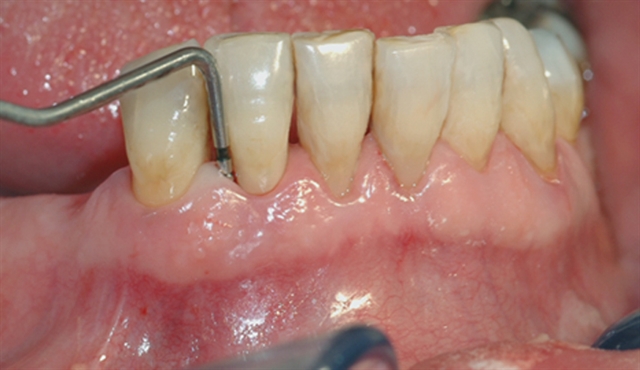

• Biletet viser tilsynelatande normale tannkjøttilhøve ved tenner i underkjeven.

• Ei undersøking med lommeregistrering avdekkjer likevel eit omfattande beintap ved den eine

tanna.